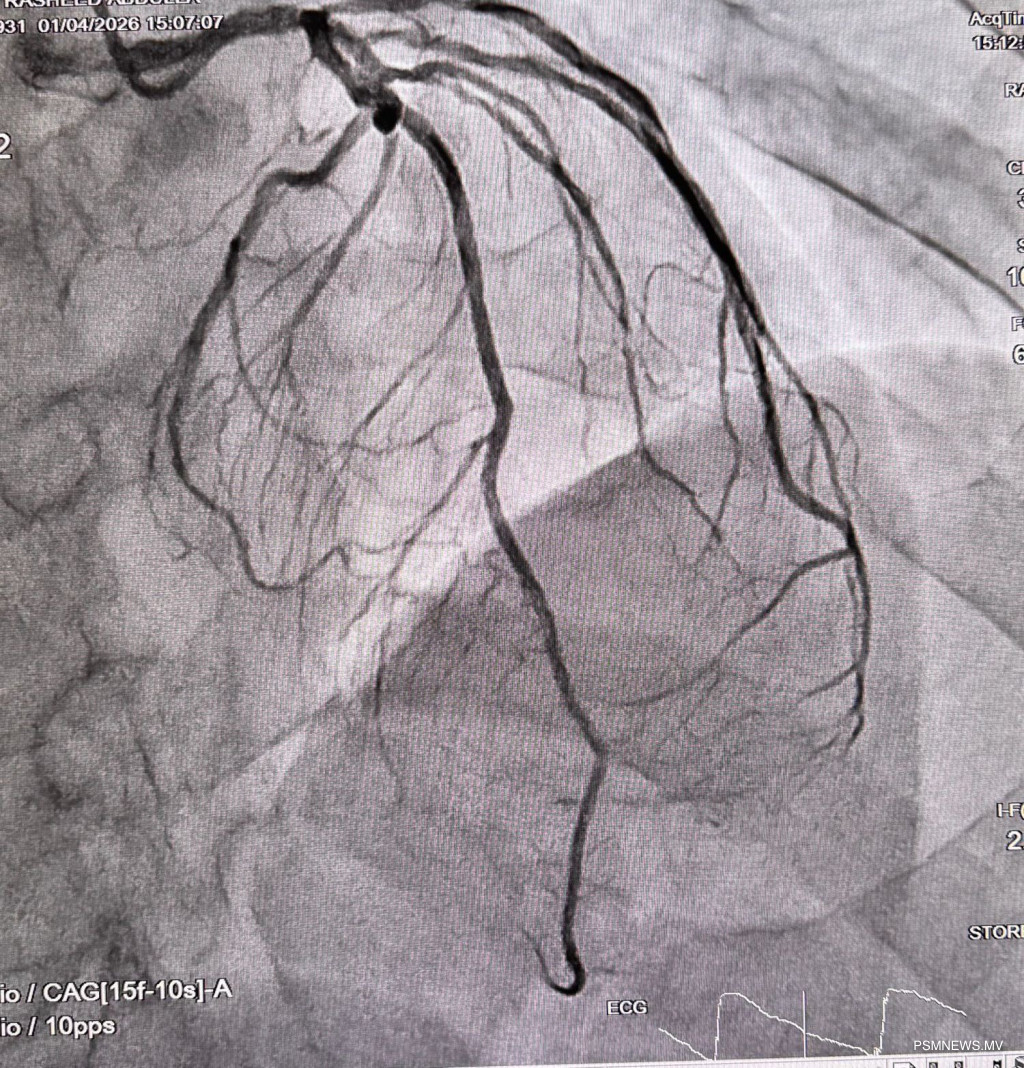

މި ދަތުރުގައި ހިތުގެ މައްސަލަތަކަށް ބޭނުންވާ މުހިންމު އެހެން ފަރުވާތައް ވެސް ތަޢާރަފުކޮށްފައިވެއެވެ. އޭގެ ތެރޭގައި "އައި.ސީ.ޑީ" އަދި "ޕާމަނަންޓް ޕޭސްމޭކަރ" ހަރުކުރުމުގެ ޚިދުމަތް ހިމެނެއެވެ. މި މުއްދަތުގެ ތެރޭގައި ޖުމްލަ 11 އެންޖިއޯގްރާމާއި 6 އެންޖިއޯޕްލާސްޓީ ހަދައި، ފުރާނަ ސަލާމަތް ކުރުމަށް ބޭނުންވާ މުހިންމު ފަރުވާތައް ވަނީ ދީފައެވެ.